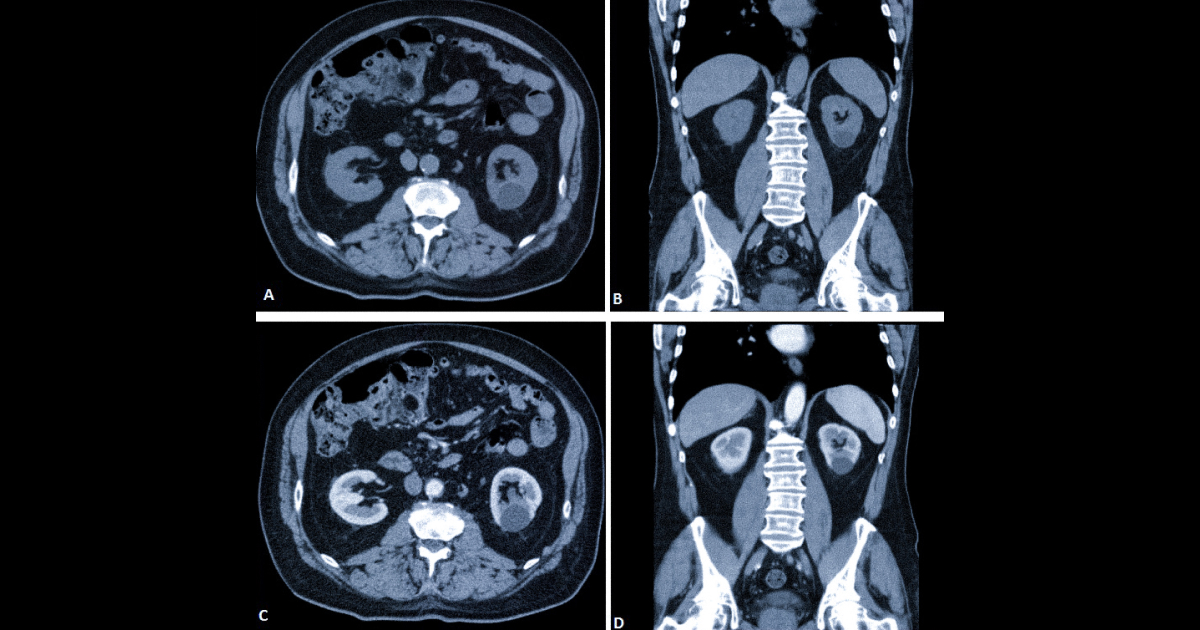

Комп’ютерна томографія дозволяє отримати детальні пошарові зображення нирок, сечоводів і сечового міхура. На відміну від ультразвуку або рентгену, КТ здатна виявляти навіть дуже маленькі камені.

Гідронефроз: коли камінь блокує відтік сечі

Одне з можливих ускладнень сечокам’яної хвороби — гідронефроз.

Це стан, при якому відтік сечі з нирки порушується через перешкоду, наприклад камінь у сечоводі. У результаті відбувається розширення ниркової миски та чашечок.

На КТ лікар може побачити:

- розширення мисково-чашкової системи,

- набряк тканини нирки,

- точне місце блокування сечоводу.

Ця інформація допомагає швидко оцінити серйозність ситуації та вирішити, чи потрібне термінове втручання.